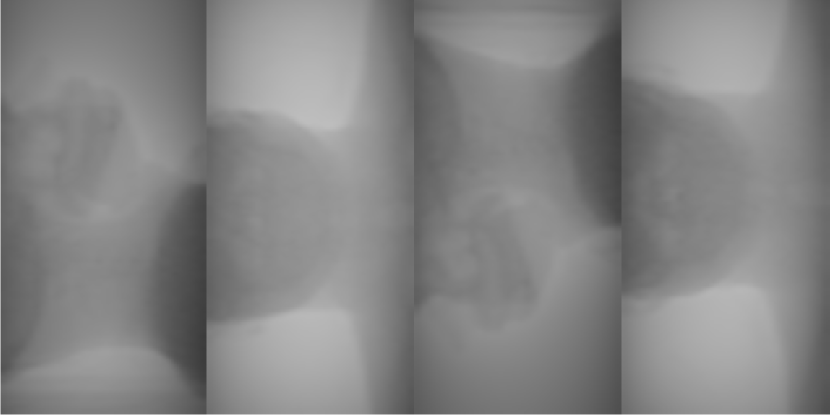

For illustrative purposes, select scatter estimates, along with the ground-truth are shown in Figure 4.

(a) Oracle scatter

(b) Uniform estimate

(c) SKS estimate

(d) ASKS estimate

(e) Online-prior-MC

(f) Offline-prior-MC

Figure 4: Examples of low-dose scatter estimates shown with grey scale [10,70]: (a) is the oracle scatter from the measurement synthesis; (b) is a uniform estimate; (c) and (d) are SKS and fASKS estimates respectively; (e) and (f) are on-line and off-line planning MC estimates respectively.